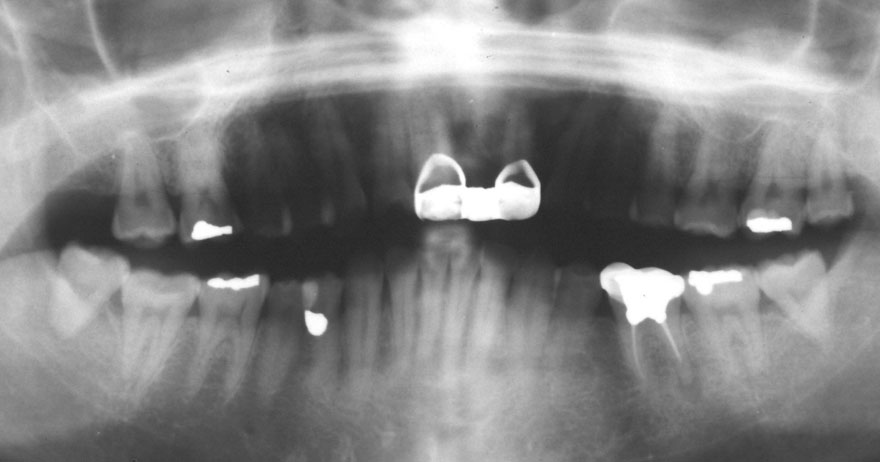

初診時 42歳 男性 平均歯槽骨喪失量:5.30mm

22年後 64歳

平均歯槽骨喪失量:5.554mm

22年間喪失量:-0.24mm

年間喪失速度:-0.01mm

(ケア頻度:1.07ヵ月ごと)